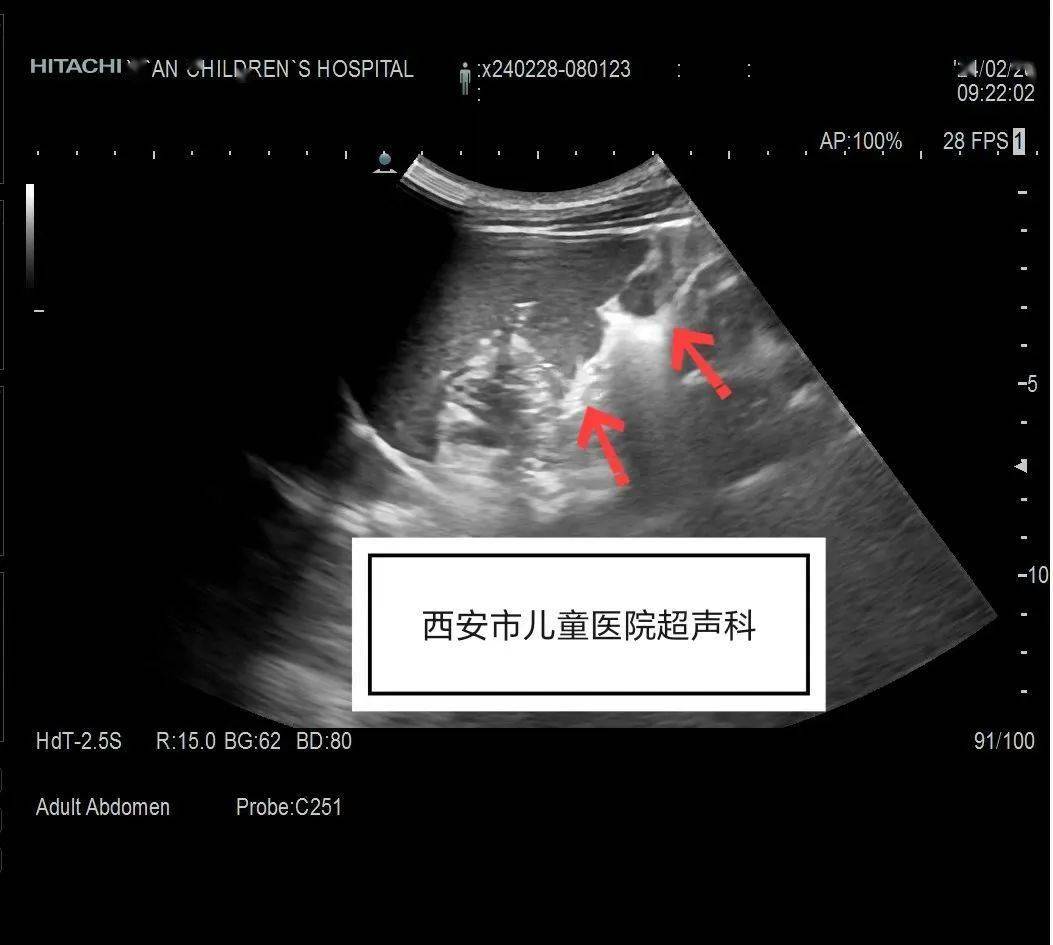

脾内占位性病变?脾囊肿?

图片尺寸640x853